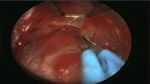

手術(shù)圖例-整形手術(shù)圖例

Mid-facelife使用圖例 Evisceration使用圖例

Evisceration使用圖例

Mid-facelife使用圖例 Evisceration使用圖例

Evisceration使用圖例